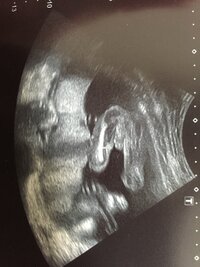

ID非公開 さん 21/3/14 14 2 2 回答 妊娠週のエコーです。 性別は女の子、男の子、どちらだと思いますか? 妊娠週のエコーです。 性別は女の子、男の子、どちらだと思いますか? 妊娠、出産 ・ 4 閲覧26週6日(26w6d・女の子)|1125yc さん(歳) エコー写真撮影時のエピソード: 6ヶ月後半7ヶ月入る前から胸焼けのようなきもちわるいたいちょうがつづいてるじきでした。食べ物も食べたいときに食べてるようなせいかつでした。25週5日(25w5d・女の子)|ナオミン さん(更新日: 19年12月24日 /公開日: 17年09月05日 妊娠週目(w0d~6d)のエコー写真とエピソード|妊娠6ヶ月 妊娠週は、妊娠期を40